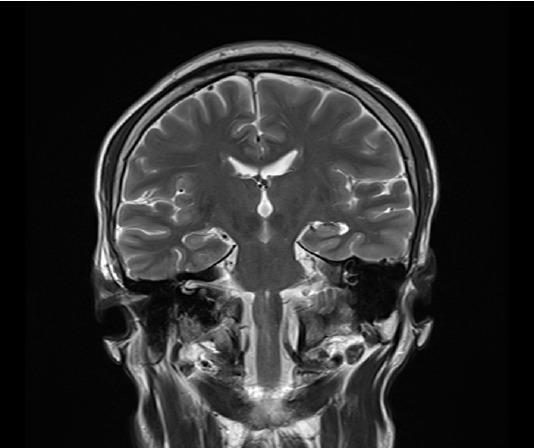

A 51-year-old man with a 10-day history of acute-onset dysphagia presented with inability to swallow anything orally. The patient was unable to swallow any radiopaque contrast medium; therefore, a videofluoroscopic swallow study could not be performed. Brain imaging, neurological findings, and initial endoscopy findings were normal. Neck computed tomography suggested left vocal cord paralysis. The patient was diagnosed with diabetes one year prior to presentation but did not receive any treatment. Insulin therapy during hospitalization controlled the patient's blood glucose levels, and his symptoms improved without any sequelae. We present a rare case of vocal cord paralysis secondary to controlled diabetes. The initial endoscopic examination did not include thorough evaluation of the vocal cords; therefore, accurate diagnosis was challenging in this case.

一名51岁男性,有10天急性发作吞咽困难病史,表现为无法口服任何东西。患者无法吞咽任何不透射线的造影剂;因此,无法进行视频透视吞咽研究。脑成像、神经系统检查结果和初步内窥镜检查结果均正常。颈部计算机断层扫描显示左声带麻痹。患者在就诊前一年被诊断为糖尿病,但未接受任何治疗。住院期间的胰岛素治疗控制了患者的血糖水平,症状得到改善,没有任何后遗症。我们报告了一例罕见的继发于控制性糖尿病的声带麻痹病例。最初的内窥镜检查不包括对声带的彻底评估;因此,在这种情况下,准确的诊断具有挑战性。